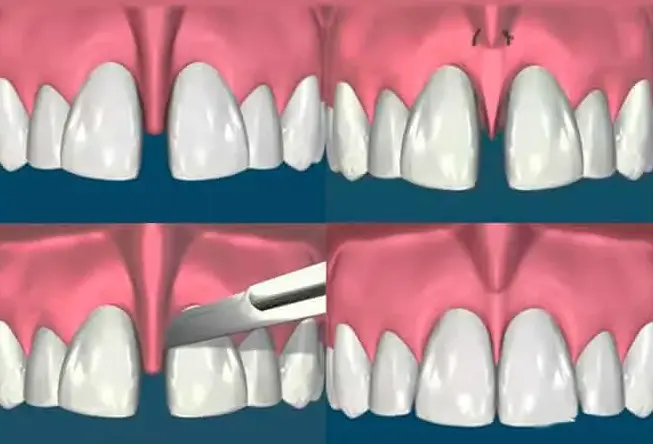

La frenectomía es un procedimiento quirúrgico sencillo realizado bajo anestesia local. Consiste en corregir la posición del frenillo, eliminando el tejido excesivo para permitir un cierre adecuado del diastema y mejorar la movilidad y funcionalidad del labio.

Durante la frenectomía, se corta y se elimina el frenillo problemático para permitir un movimiento normal del labio o la lengua, según sea el caso. Una vez eliminado el frenillo, se sutura la incisión y se proporcionan instrucciones postoperatorias para la adecuada cicatrización y recuperación del área intervenida.

La frenectomía es una intervención relativamente simple y segura que puede tener beneficios significativos para la salud y la calidad de vida del paciente, mejorando la estética dental, la función del habla y la higiene bucodental.